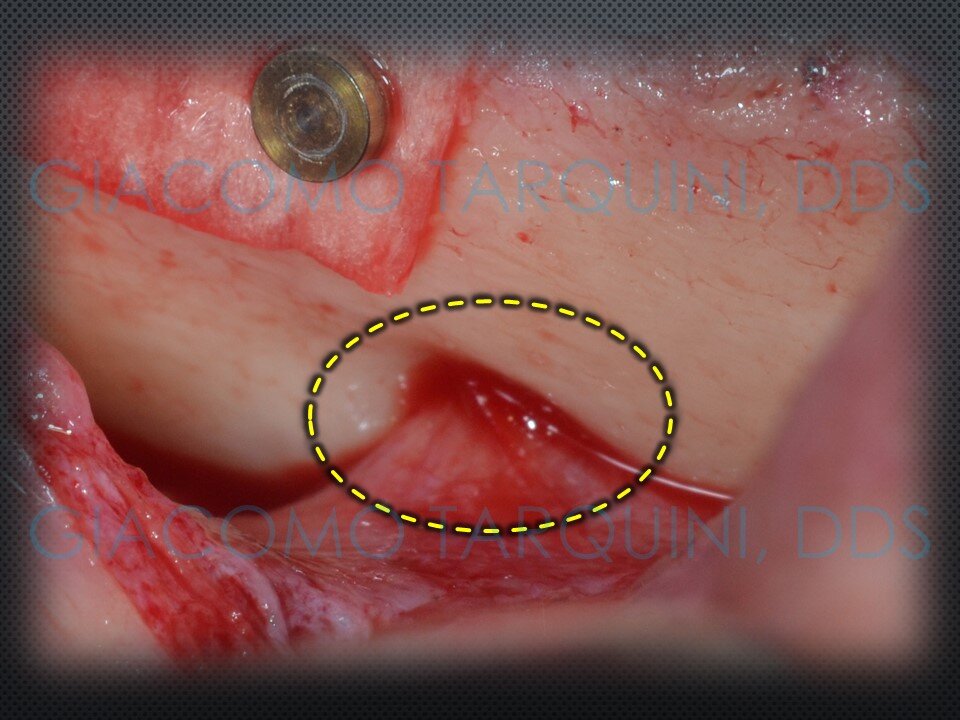

CASO CLINICO

Il caso clinico illustra il trattamento chirurgico-rigenerativo di un impianto endosseo affetto da peri-implantite effettuato secondo il protocollo «PIEZOCLEAN by Dr. Giacomo Tarquini»

- Rimuovere la vite di copertura (ove presente) allo scopo di decontaminare anche la superficie interna dell’impianto e sostituirla con una sterile al termine di questa fase operatoria